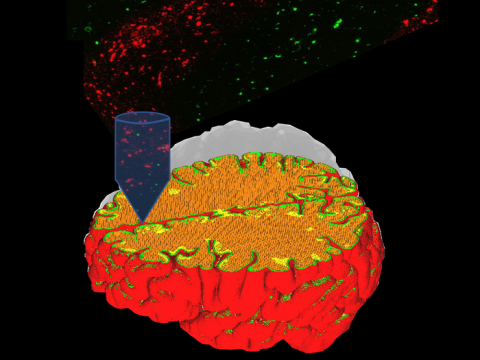

- 斯坦福大学如何加快3D打印心脏?

- 中国团队「六轴细胞3D打印机」登顶刊!心肌组织体外存活超6个月

- 中科院科学家在改良的生物打印机上3D打印出正在跳动的心脏

- 6自由度的全新机器人手臂,协同3D打印铸造可以跳动的心肌组织